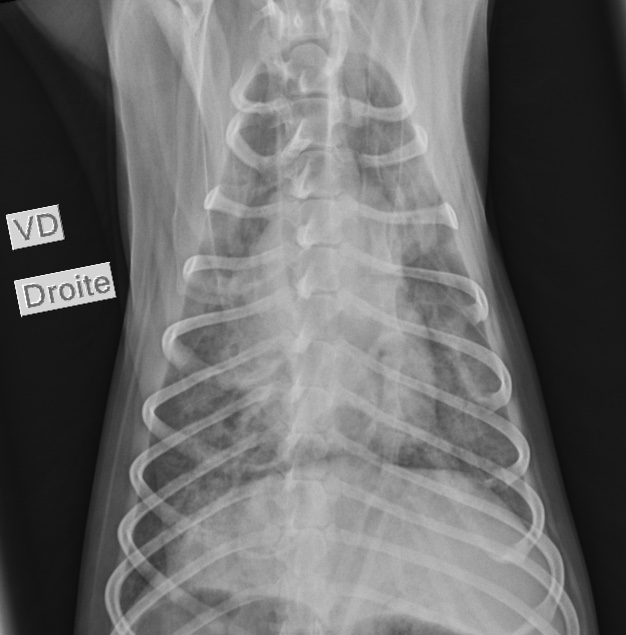

Des radiographies du thorax sont réalisées (figures 1 et 2).

1 . Interprétez les radiographies du thorax – Quels sont les hypothèses diagnostiques à envisager au vu de ces radiographies ?

Au niveau des structures extra thoraciques, nous observons un contenu aérique dans l’estomac.

Au niveau des structures intrathoraciques, nous notons aucune anomalie au niveau de l’espace pleural, du médiastin et au niveau des structures cardiovasculaires (indice de Buchanan à 9,6). Au niveau du parenchyme pulmonaire, nous observons une opacification interstitielle diffuse sévère et plus marquée aux lobes caudaux dorsaux. Des zones multifocales d’opacifications alvéolaires sont observées et masquent par endroits la silhouette cardiaque (figure 3).

L’affection est localisée aux voies respiratoires profondes (bronches, bronchioles, alvéoles, parenchyme pulmonaire). L’œdème aigu du poumon cardiogénique est exclu par une auscultation cardiaque sans anomalie et des structures cardio-vasculaires normales aux radiographies. Le chien est jeune et ne fait pas parti des races prédisposées pour les causes inflammatoires (bronchite éosinophilique…), dégénératives et néoplasiques. L’œdème aigu du poumon non cardiogénique, des coagulopathies et des causes traumatiques semblent moins probables du fait de la chronicité des évènements. Le contexte anamnestico-clinique nous oriente donc vers une pneumonie infectieuse.